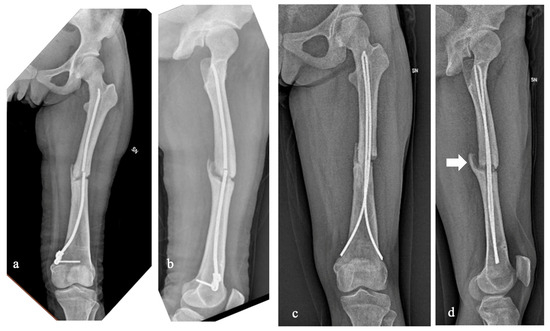

The intrinsically altered clastic functions affect physiological bone healing processes [20,26,27]. In our experience, the rate of delayed union and nonunion were both fairly high. Case 5 had a displaced diaphyseal left femur fracture that was intramedullary treated with a single elastic nail at a different hospital (Figure 3). The fracture never healed, and, as a result of a low-energy traumatic event, the femur refractured at the pseudoarthrosis site with associated internal device breakage. The patient then came to our attention, and we decided to treat the refracture again with an intramedullary device in order to be minimally invasive. To prevent reaming complications and due to the small size of the femur, we decided to use two 4 mm titanium elastic nails placed with the ESIN standard technique. Within a year from the surgery, despite the patient’s overall good recovery for common daily life activities, X-rays showed a hypertrophic pseudoarthrosis that will require a new surgery. Therefore, despite the fact that the stature and the weight of the patient were compatible with the ESIN technique, the patient’s age, the underlying bone disease, and the previous history of pseudoarthrosis can be considered consistent unfavorable elements. We have no direct experience of treating pseudoarthrosis with autologous bone grafts in PYCD. However, our indirect experience (Case 1) is positive, such that we could consider it a viable option for additional surgical time in Case 5.

Figure 3. Case 5 had a displaced diaphyseal left femur fracture that never healed and, as a result of a low-energy traumatic event, the femur refractured at the pseudoarthrosis site with associated nail breakage (a,b). We decided to treat the refracture with two 4 mm titanium elastic nails placed with the standard technique (ESIN, elastic stable intramedullary nailing). Within a year from the surgery, the X-rays showed a hypertrophic pseudoarthrosis (arrow) that will require a new surgery (c,d).